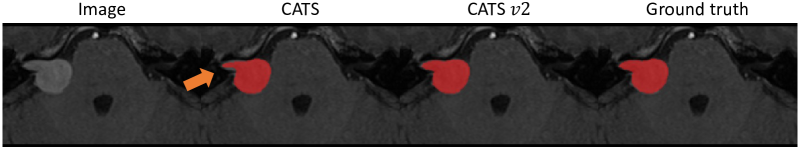

The quantitative results for the CrossMoDA dataset are presented in Tab. 2. We compare the models against a 2.5D CNN model [33], which was specifically designed to segment VS from MRIs characterized by substantial discrepancies between in-plane resolution and slice thickness, which is a common feature of this dataset. We observe that this CNN-only network performs better than the transformer-based encoders [12, 13] for this task. The original CATS [20] model outperformed the 2.5D CNN. With subsequent enhancements, our updated CATS v2 model further refined the quality of segmentation, delivering the highest performance in terms of Dice score. Fig. 3 shows the qualitative results of VS segmentation. While the original CATS model undersegments the VS (marked by arrow), the proposed CATS v2 effectively compensates for this limitation and produces robust results that align more closely with the ground truth segmentations.